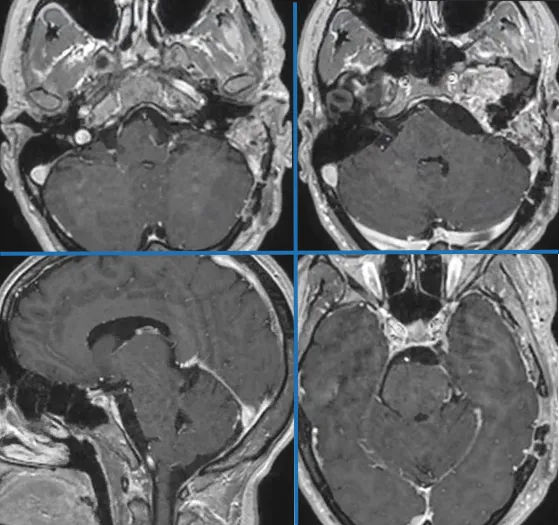

本例手术中,INC福教授采用经典颞-顶-枕L形开颅联合精细岩骨切除术。手术初始通过识别关键骨性标志、实施整形性乳突切除术并充分显露乙状窦与窦硬膜角,构建坚实手术基础。

随后通过精准前岩骨切除术,逆向追踪识别岩浅大神经等重要结构,并显露包含道后三角的菱形区域,为抵达深部病灶开辟通道。继而通过切开颞部与后颅窝硬脑膜、离断天幕并使横窦-乙状窦交界区后移,成功创建宽阔手术路径。

肿瘤切除在多视角下于蛛网膜下腔内精细进行,通过锐性解剖实现梅克尔腔等处肿瘤全切,并全程注重保护第IV、VI颅神经及下组颅神经。最终使用帽状腱膜移植物与腹部脂肪严密修补硬脑膜缺损,完成骨瓣复位固定,肿瘤获得顺利切除。

术后MRI确认肿瘤切除效果。